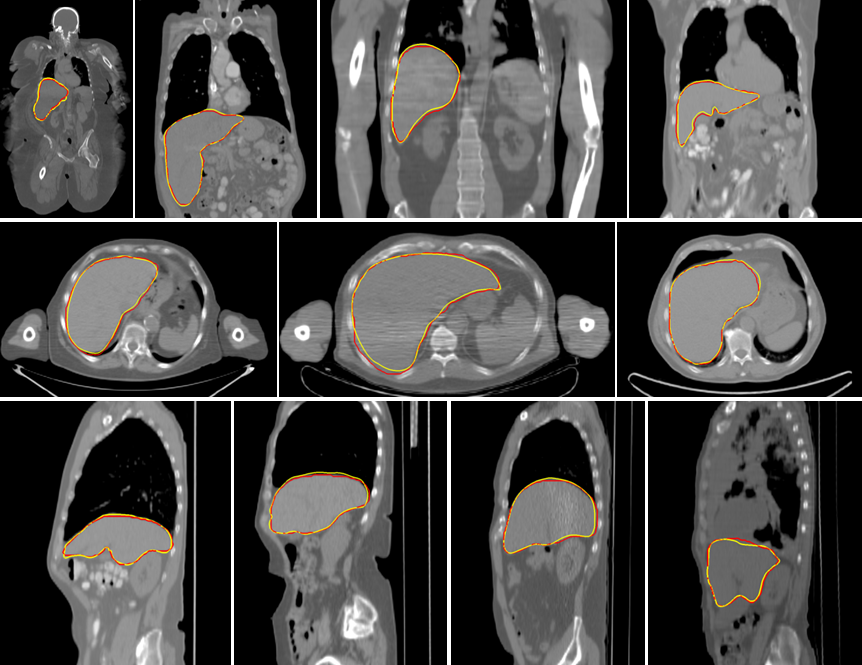

Table 1 compares the performance of five different methods. The first method, the hierarchical, learning-based algorithm proposed in [5], was trained using 400 CT volumes. More training data did not show performance improvement for this method. For comparison purpose, the DI2IN network, which is similar to deep learning based algorithms proposed in [6, 7, 8] without post-processing steps, and the DI2IN-AN were trained using the same 400 cases. Both the DI2IN network and the DI2IN-AN were also trained using all 1000+ CT volumes. The average symmetric surface distance (ASD) and dice coefficients are computed for all methods on the test data. As shown in Table 1, DI2IN-AN achieves the best performance in both evaluation metrics. All deep learning based algorithms outperform the classic learning based algorithm with the hand-craft features, which shows the power of CNN. The results show that more training data enhances the performance of both DI2IN and DI2IN-AN. Take DI2IN for example, training with 1000+ labelled data improves the mean ASD by 0.23mm and the max ASD by 3.84mm compared to training with 400 labelled data. Table 1 also shows that the adversarial structure can further boost the performance of DI2IN. The maximum ASD error is also reduced. Typical test samples are provided in Fig. 4. We also tried CRF and graph cut to refine the output of DI2IN. However, the results became worse, since a large portion of testing data had no contrast and the boundary of liver bottom at many locations was very fuzzy. CRF and graph cut both suffer from serious leakage in these situations. Using an NVIDIA TITAN X GPU and the Theano/Lasagne library, the run time of our algorithm is less than one second, which is significantly faster than most of the current approaches. For example, it requires 1.5 minutes for one case in [6]. More experimental results can be found in the supplementary material.